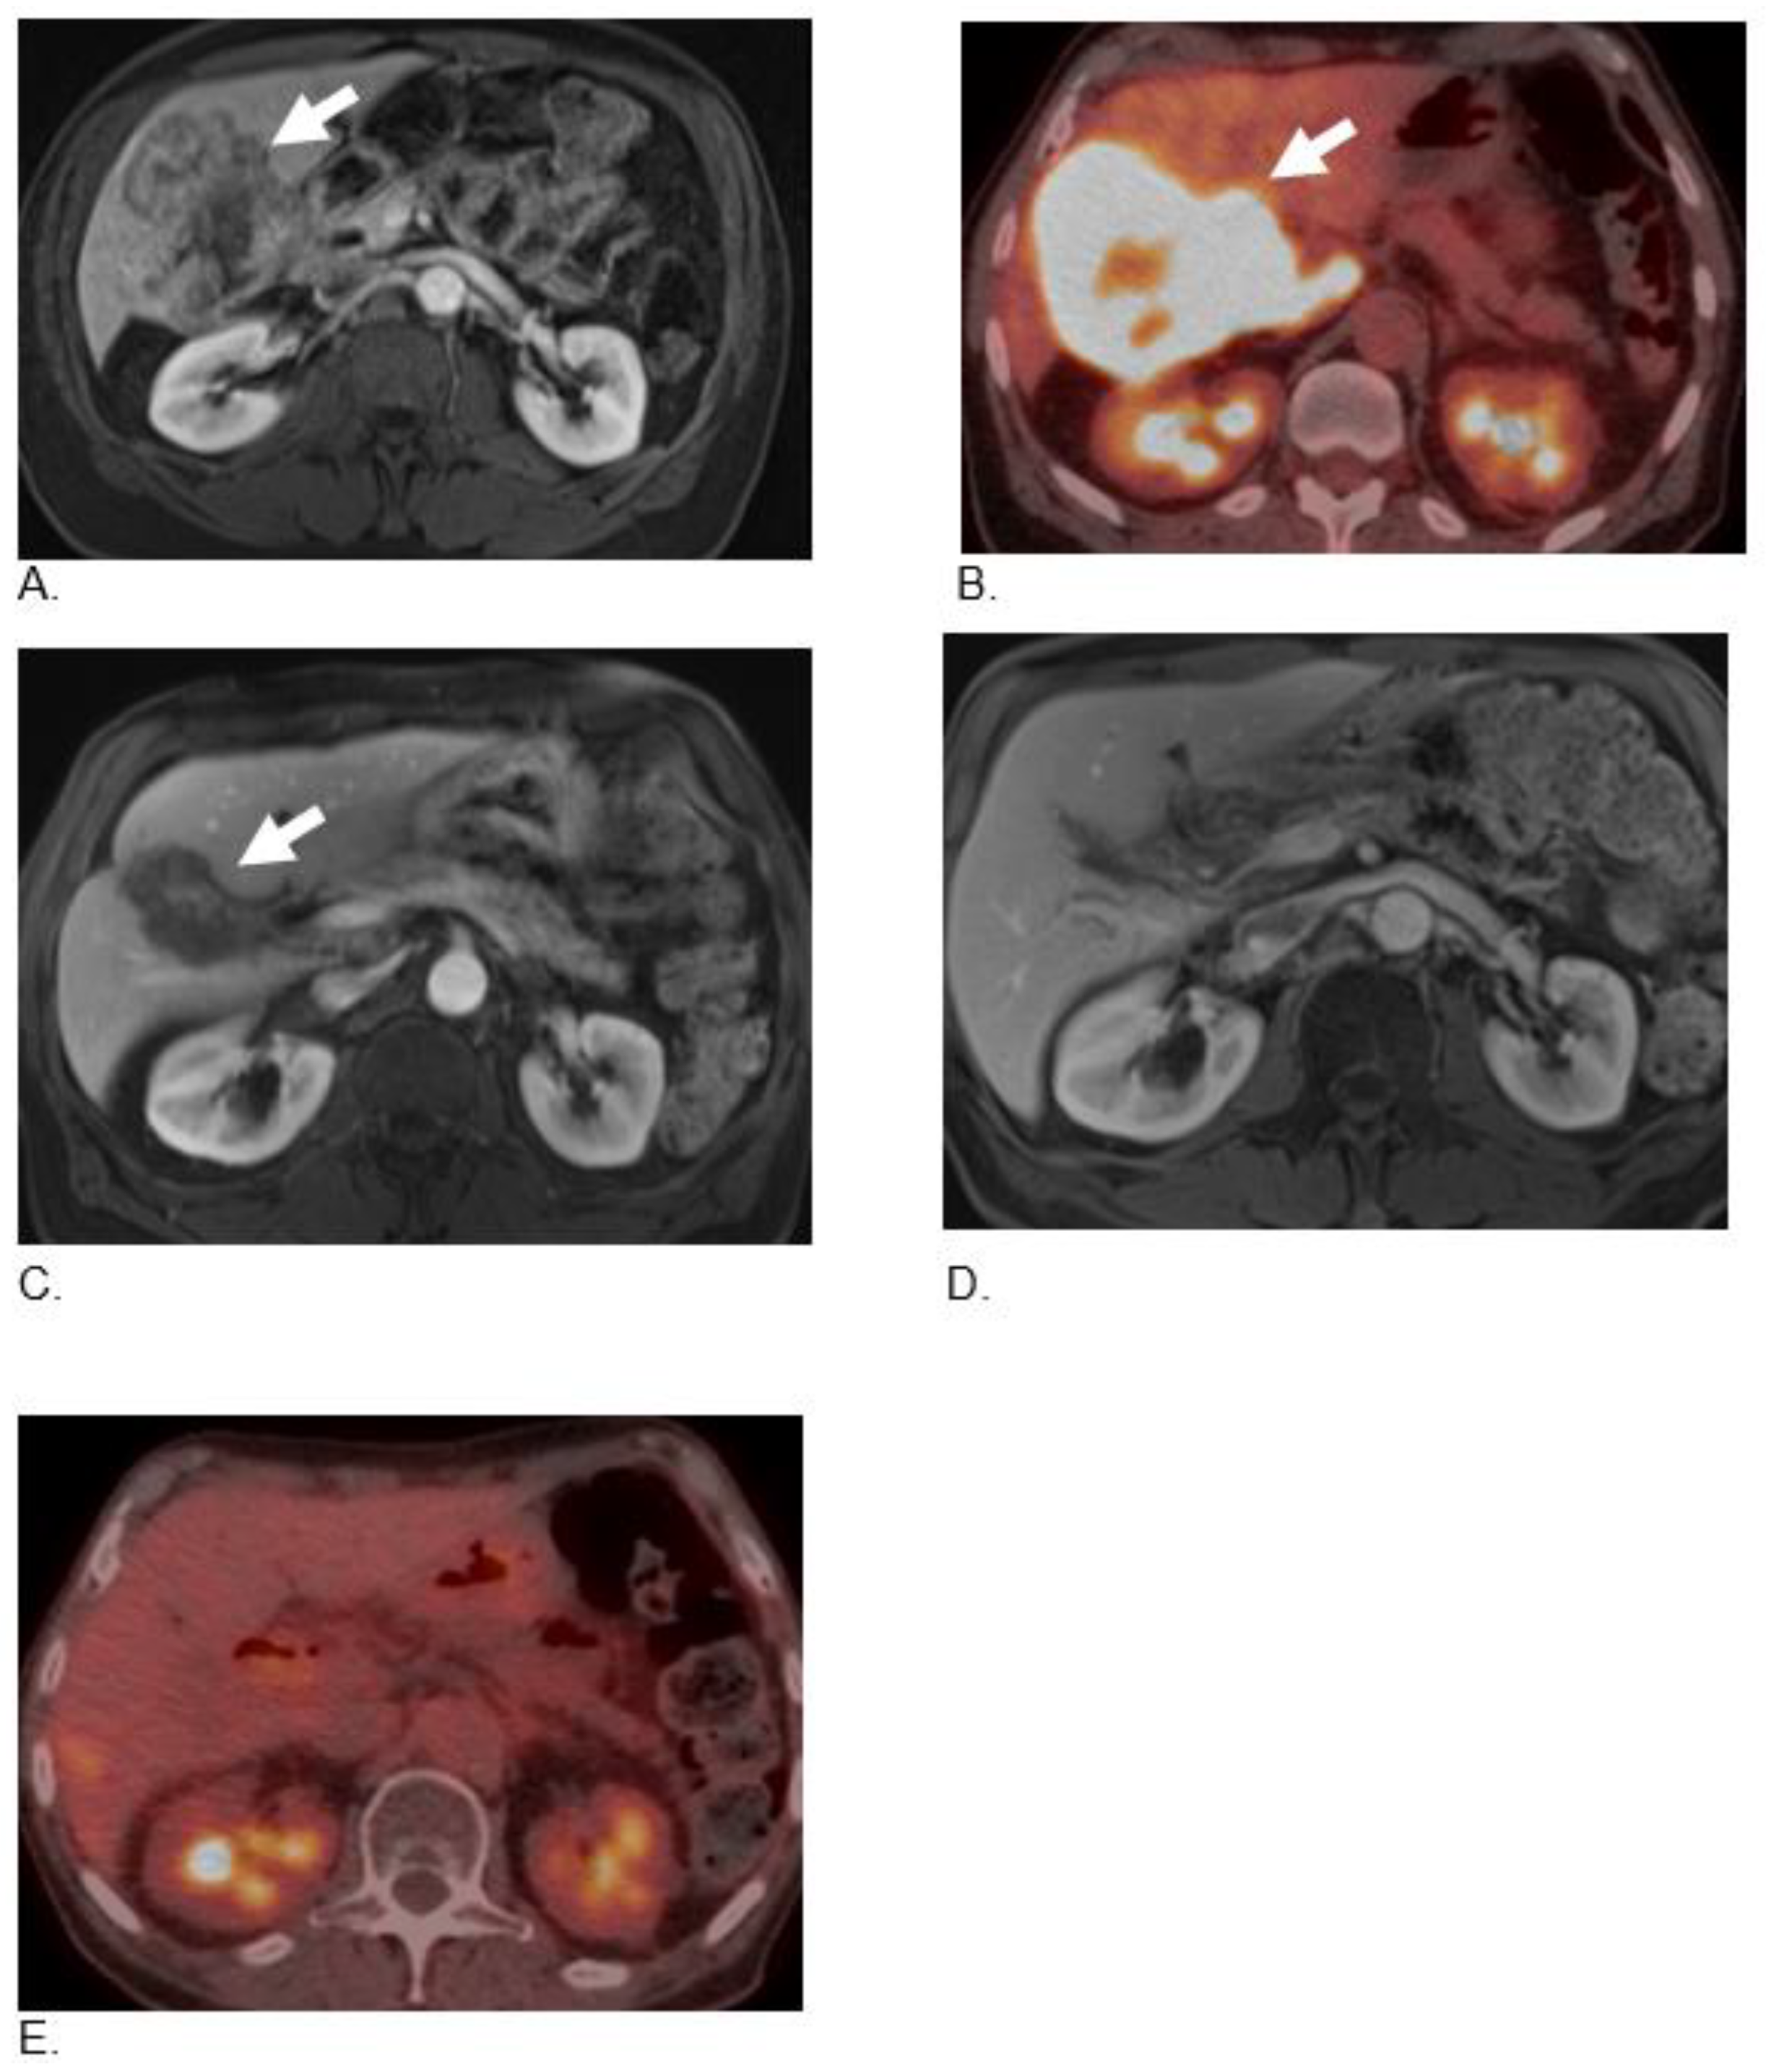

| Unknown Primary | EP Poorly differentiated neuroendocrine carcinoma (Small cell) | 77 | M | Carboplatin and Etoposide | Nivolumab 240 mg intravenous (i.v) every 2 weeks and Ipilimumab 1 mg/kg i.v. every 6 weeks for 4 cycles plus TQ-BSO (3 tablets 500 mg daily) | Nivolumab 240 mg i.v. every 2 weeks, plus BSO (TQ) tablets 1500 mg daily | Alive with PR and PFS of 24 mos |

| Gall Bladder | Poorly differentiated neuroendocrine carcinoma (Small cell) | 75 | M | Carboplatin and Etoposide | Nivolumab 3 mg/kg i.v and Ipilimumab 1 mg/kg i.v. every 3 weeks for 4 cycles plus TQ-BSO (3 tablets 500 mg daily) | Nivolumab 240 mg i.v. every 2 weeks, plus BSO (TQ) tablets 1500 mg daily | Alive with CR and PFS of 22 mos |

| Colon MiNEN | Mixed neuroendocrine-non-neuroendocrine neoplasm (MiNEN). | 67 | M | Carboplatin and Etoposide | Nivolumab 3 mg/kg i.v and Ipilimumab 1 mg/kg i.v. every 3 weeks for 4 cycles plus TQ-BSO (1 teaspoon oil formula daily) | Nivolumab 240 mg i.v. every 2 weeks plus BSO (TQ) tablets 1500 mg daily | Alive with CR and PFS of 10 mos |

| Colon MiNEN | Mixed neuroendocrine-non-neuroendocrine neoplasm (MiNEN). 70% small cell and 30% adenocarcinoma | 85 | M | Adjuvant mFOLFOX | Nivolumab 3 mg/kg i.v and Ipilimumab 1 mg/kg i.v. every 3 weeks for 3 cycles plus TQ-BSO (3 tablets 500 mg daily) | BSO (TQ) tablets 1500 mg daily | Alive with PR and PFS of 12 month |